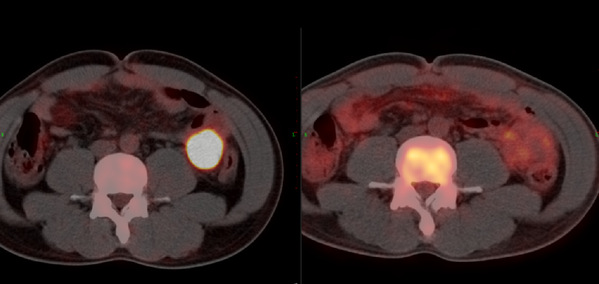

After being diagnosed with diffuse large B-cell lymphoma more than 4 years ago, Mr. Sun has gone through a long and painful treatment includ...